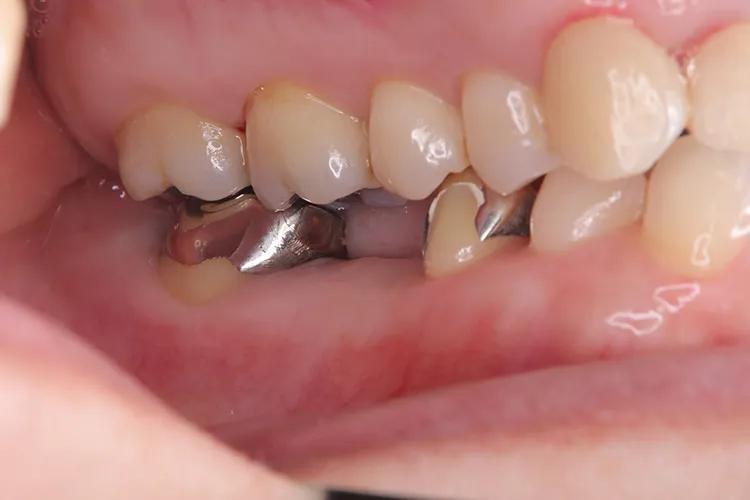

左下5本欠損した部分をインプラント3本埋入して5本ブリッジで治したケースです。なかなかインプラントに踏み切れず、長い間入れ歯を使っておられましたが、噛みごたえがなく好きなものが食べれない上に、度々歯茎が痛んでは調整の繰り返しで快適に過ごすことができず、QOLの向上のためインプラント治療を決断されました。今ではなんでも食べれるとのことで、入れ歯で我慢しないでもっと早くインプラントにすればよかったと言っておられます。